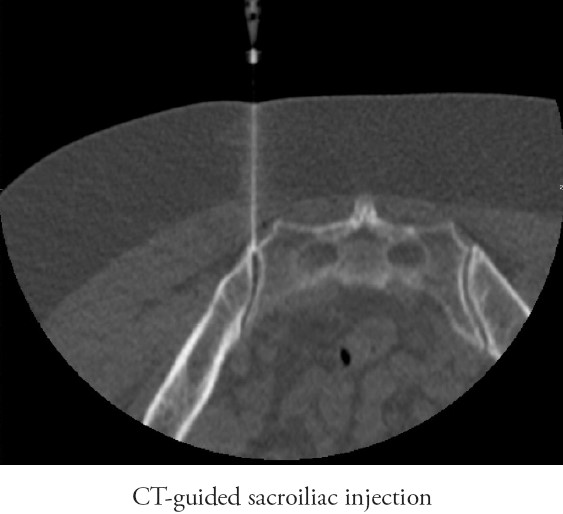

Sacroiliac Joint Injection How Much Does A Ct Guided Injection Cost Near New South Wales ct guided injections are procedures where a ct scanner is used to guide a needle to a location in the body so that a medication. Spinal interventional injections are one of the pain management procedures we offer. ct guided injections are used to deliver medications straight into an area (typically back and neck) that is effected by. It. How Much Does A Ct Guided Injection Cost Near New South Wales.